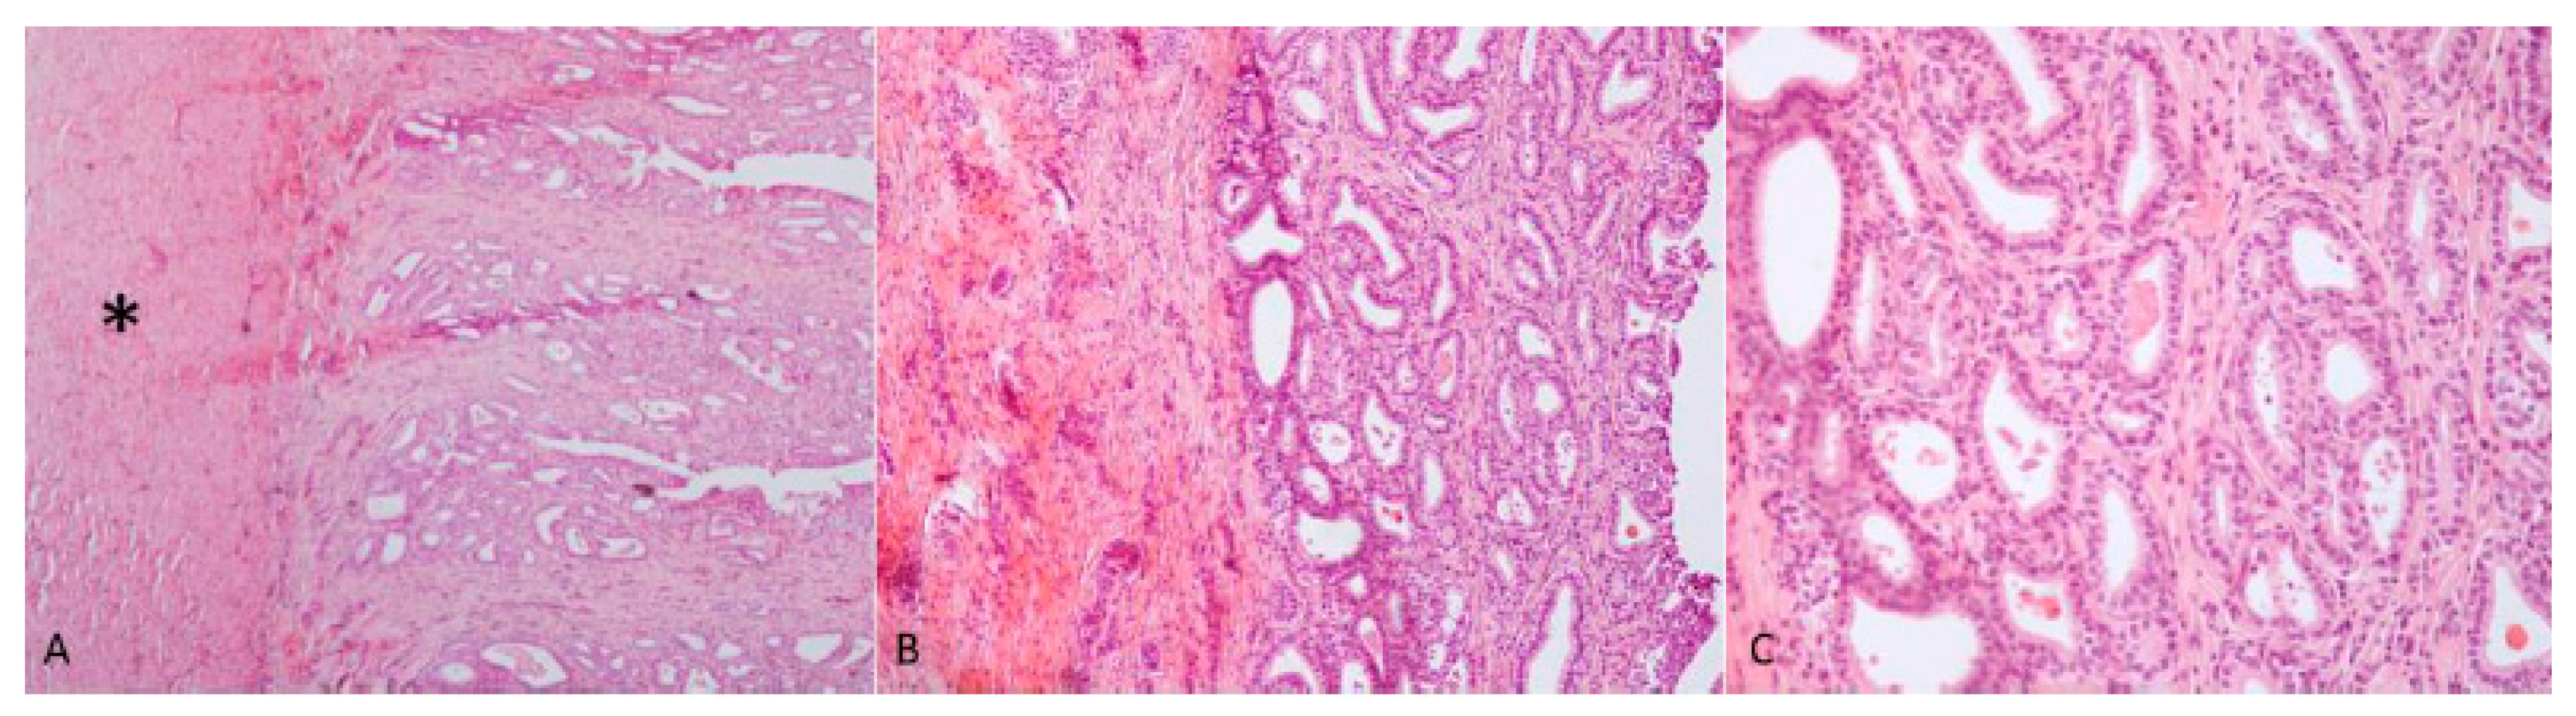

Case 1: The testes were grossly enlarged up to two or three times their normal size (25 × 20 cm). In the cut surface, there was a massive abscess and severe, diffuse, dry, grey-yellow necrosis resulting in the complete destruction of testicular parenchyma (Figure 1C). The epididymis was characterized by foci of diffuse thickening and fibrinous adhesions of the testicular vaginal tunics. Fibrotic tissue was also adherent to the tunic and scrotum. A tubular structure of small diameter with a cul-de-sac end and attached to the testis was observed. This structure was soft at sectioning, and the internal wall showed a diffusely pink surface and no fluid in the lumen (Figure 1D). Histological examination of the testis and epididymis revealed a diffuse area of caseo-necrosis, effacing 98% of the normal architecture and compressing, separating, surrounding and replacing the seminiferous tubules (Figure 5A). Necrotic debris was admixed with degenerate neutrophils, encircled by foamy macrophages (Figure 5B) and occasionally surrounded by granulation tissue and abundant collagen (fibrosis). In the remaining seminiferous tubules, there was diffuse germ cell atrophy with lack of spermatids. Epidydimal epithelia were surrounded by a mild, chronic, inflammatory infiltrate consisting mostly of lymphocytes and associated with severe fibrosis (Figure 5C). Microscopic examination of the tubular structure was interpreted as a uterine tube characterized by an outer layer of connective and hypo-trophic muscle tissue with few vessels and an inner layer compatible with endometrium (Figure 6A). The endometrial tissue was characterized by a stratified epithelium with numerous simple and slightly hyperplastic tubular uterine glands (Figure 6B,C). No ovarian tissue was macroscopically and microscopically visible.

Figure 5. (A,B) Diffuse caseo-necrotic areas were admixed with degenerate neutrophils and surrounded by foamy macrophages. Normal parenchyma was almost totally replaced by necrosis and inflammation; (C) chronic epididymitis with inflammatory infiltrate consisting mostly of lymphocytes associated with interstitial fibrosis and epididymal epithelial mild hyperplasia. Haematoxylin and eosin staining.